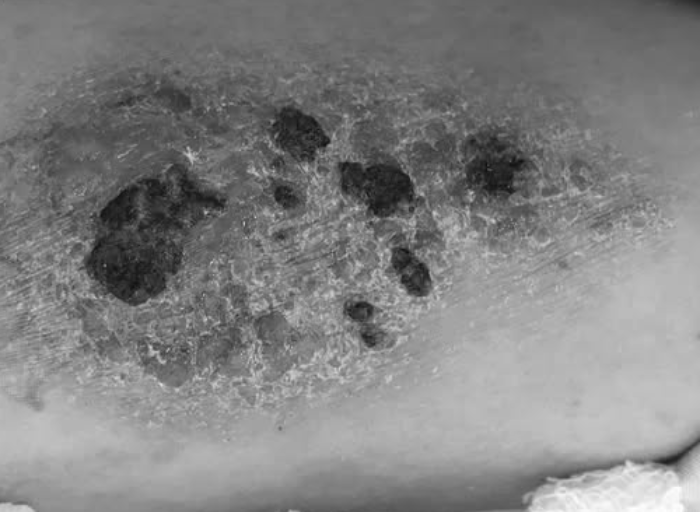

Ngày 20/8, Bệnh viện Da liễu TPHCM cho hay gần đây tiếp nhận nhiều ca biến chứng sau xăm hình như nhiễm vi khuẩn lao, phát ban dạng sẩn nốt, phản ứng u hạt, sẹo (sẹo lồi, lõm, sẹo xấu), ung thư da.

Trường hợp biến chứng muộn (mạn tính), các dấu hiệu thường xuất hiện sau vài tháng - năm. Các bệnh lý như nhiễm vi khuẩn lao điển hình hoặc không điển hình, phát ban dạng sẩn nốt, phản ứng u hạt, sẹo (sẹo lồi, lõm, sẹo xấu), thậm chí ung thư da.